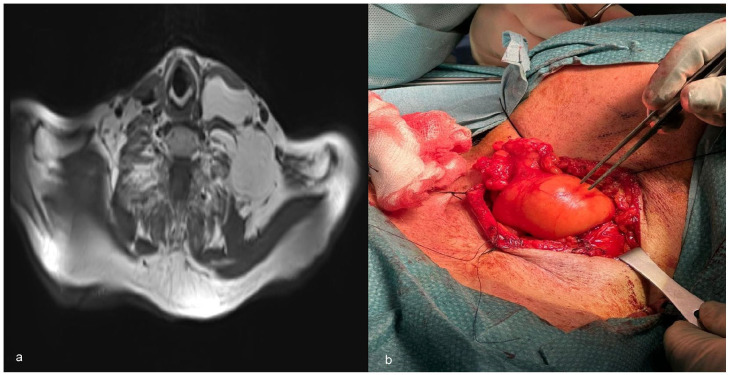

肌内脂肪瘤通常发生在皮下组织,很少影响深层肌肉平面,尤其是头颈部。以下是 3 例涉及胸锁乳突肌的肌肉内脂肪瘤病例。前两名患者表现为无痛、可触及的肿块,经影像诊断证实为环绕性肌内脂肪瘤。其中一名患者接受了手术治疗,另一名患者接受了保守治疗,并进行了监测和密切随访。第三位患者报告吞咽困难,并伴有偶尔的呼吸困难和轻微疼痛。肿块被确定为浸润性脂肪瘤,并进行了手术切除。第一例和最后一例患者的肿瘤完全切除,6 个月后无复发。对第二个病例进行了 3 个月和 6 个月的连续随访,结果没有发生间隔变化。我们报告了胸锁乳突肌肌内脂肪瘤的最大病例系列,以加深我们对这一罕见病例的了解。

Intramuscular lipomas, typically found in subcutaneous tissue, rarely affect deeper muscular planes, especially those of the head and neck region. The following are 3 cases of intramuscular lipomas involving the sternocleidomastoid muscle. The first 2 patients presented with painless, palpable masses confirmed by diagnostic imaging as well-circumscribed intramuscular lipomas. One was treated surgically, while the other was managed conservatively with monitoring and close follow-up. The third patient reported dysphagia associated with occasional dyspnea and mild pain. The mass was identified as infiltrative lipoma and was resected surgically. Complete tumor removal with no recurrence at 6 months was observed for the first and last cases. The second case was serially followed at 3 and 6 months with no interval changes. We report the largest case series on intramuscular lipomas of the sternocleidomastoid muscle to enhance our understanding of this rare entity.